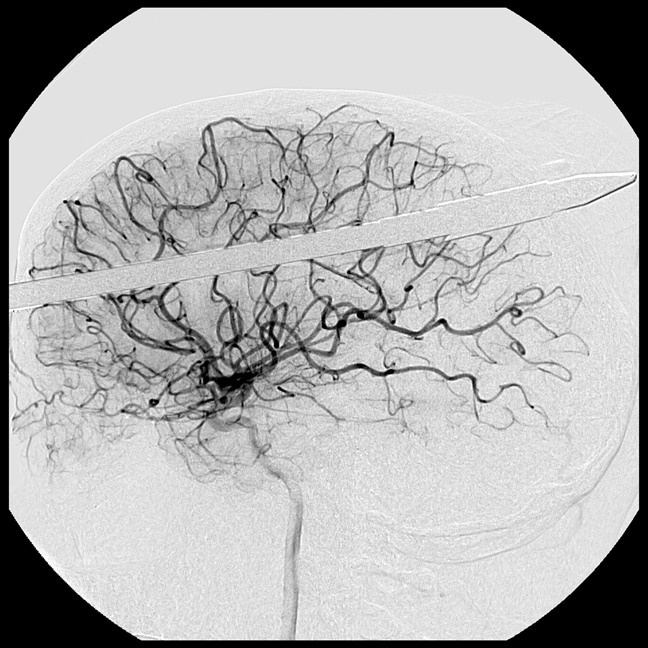

Για να μην τραυματιστεί χειρότερα, ακινητοποιήθηκε χημικά όσο οι γιατροί εξέταζαν το πώς θα αφαιρούσαν το καμάκι από το κεφάλι του. «Είναι θαύμα που δεν χτυπήθηκε κανένα από τα βασικά αιμοφόρα αγγεία του εγκεφάλου», δήλωσε ο νευροχειρουργός Ross Bullock. «Το πιο δύσκολο είναι να αντισταθείς στον πειρασμό να τραβήξεις αυτό το πράγμα έξω».

Αντίθετα οι γιατροί σταθεροποίησαν το καμάκι και απομάκρυναν κομμάτι μήκους 47 εκατοστών, πριν βγάλουν τις ακτινογραφίες. Χρειάστηκαν στη συνέχεια τρεις ώρες για να απομακρύνουν τη λόγχη από τον Lopez, ο οποίος νοσηλεύεται σε σοβαρή αλλά σταθερή κατάσταση.